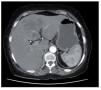

Mujer de 73 años de edad, originaria de San Luis Potosí, México, con antecedentes de tabaquismo, hipertensión arterial, diabetes mellitus e histerectomía 15 años antes de este cuadro clínico. Acudió a consulta manifestando tres semanas de cefalea, nausea, vómito y perdida de peso mayor a 5 kg acompañando a un dolor persistente y progresivo en epigastrio y episodios de fiebre de hasta 39° C. A la exploración física se encontró con el abdomen blando y doloroso a nivel de hipocondrio derecho, sin detectar hepatomegalia ni masas palpables, con perístalsis presente y un ganglio palpable de 1 cm en cadena inguinal izquierda. Los exámenes de laboratorio mostraron leucocitos de 12 800 células/mm3 con una cuenta total de 11 900 polimorfonucleares/mm3 y plaquetas de 140 000/mm3. Otros examenes relevantes incluyeron glucosa de 173 mg/dL, colesterol sérico de 126 mg/dL, albumina sérica de 2.2 gr/dL, bilirrubina total de 7.28 mg/dL bilirrubina indirecta 5.8 mg/dL, fosfatasa alcalina de 383 UI/L, alaninaminotransferasa de 56 UI/L y alfa-fetoproteína 1.17 UI/mL. El examen de seroameba fue positivo a título de 1:32. Ultrasonido de abdomen superior demostró una lesión redondeada de aproximadamente 6 cm de diámetro, con un halo hipoecoico en la periferia de la lesión. La valoración radiológica fue complementada con una tomografía abdominal (Figura 1), la cual demostró múltiples lesiones hepáticas hipodensas con septos en su interior, con bordes que reforzaron con el contraste administrado lo que se interpretó como sugestivo de un absceso atípico. Con los datos obtenidos se decidió realizar una biopsia por aspiración con aguja fina de la lesión hepática. El análisis histológico mostró infiltrado de leucocitos formados por filamentos ramificados moderadamente basofilos dispuestos en forma concéntrica compatibles con las obtenidas por tinción de Gomori Grocott (Figuras 2 y 3), datos compatibles con infección por Actinomices. Con este diagnóstico se inició terapia con base en amoxicilina-clavulanato, por vía intravenosa, a dosis de 875 mg - 125 mg cada 12 horas y administrado por 10 días. Al presentar mejoría clínica satisfactoria la paciente fue egresada y continúo recibiendo tratamiento por vía oral. Su seguimiento clínico al cuarto mes de tratamiento incluyó un ultrasonido, el cual demostró reducción en las dimensiones del absceso a dos por dos centímetros de diámetro; las pruebas de funcionamiento hepático resultaron entonces normales. La paciente se mantuvo en seguimiento en otra institución durante nueve meses refiriéndose asintomática durante todo ese periodo. La paciente falleció luego de 19 meses de seguimiento, documentando como causa de defunción, un infarto agudo del miocardio.

¿ Figura 1. TC con contraste: Múltiples lesiones hepáticas hipodensas, con septos en su interior, compatibles con absceso.

La localización de la Actinomicosis puede ser cervicofacial (56%), torácica (15%) o abdominal (22% a 56%). La forma abdominal intestinal se ha descrito con presentación ileocecal (65%) o de recto sigmoides (20%) mientras que la presentación hepática se ha informado en 15% de las afecciones intra-abdominales y representa 5% de los casos con Actinomicosis.5-7 La evolución clínica temprana suele ser silente e inespecífica, con una diseminación a hígado usualmente por vía de la vena porta a partir de una fuente intestinal, aunque también puede ocurrir por extensión directa o diseminación hematógena a través de la arteria hepática. La presencia de dolor abdominal, fiebre, pérdida de peso, anemia y leucocitosis son datos comunes en la presentación abdominal compatibles con la presentación clínica de nuestra paciente.8 El signo clínico más frecuente es la palpación de una masa abdominal, sin encontrarse en todos los casos. Frecuentemente la actinomicosis abdominal ocurre como consecuencia de un traumatismo contuso, perforación intestinal o manipulación quirúrgica, y dadas las características de crecimiento lento de la bacteria pueden pasar años para la aparición clínica de la enfermedad. Se ha descrito también una mayor incidencia de estas infecciones en pacientes inmunosuprimidos.9 En la tomografía computarizada la enfermedad suele aparecer como una masa de patrón sólido o compleja con áreas quísticas, con una pared engrosada hipercaptante a la administración de contraste.9-11 Por radiología, las lesiones con frecuencia se describen como una masa de carácter infiltrativo, extra o intraluminal, acompañada de una llamativa reacción desmoplásica que en ocasiones puede dificultar el diagnóstico diferencial con un proceso maligno. La histopatología que se ha descrito en el absceso hepático por actinomices es infiltrado de leucocitos con pequeños gránulos amarillos ("gránulos de azufre"), que están formados por filamentos ramificados moderadamente basofilos dispuestos en forma concéntrica compatibles con las obtenidas por tinción de Gomori Grocott (Figuras 2 y 3). El tratamiento de elección es la penicilina. En la mayoría de los informes se acepta el antibiótico sea administrado por vía intravenosa durante dos a seis semanas reservando periodos mas largos para pacientes con cuadro clínico mas grave y la vía oral por seis a 12 meses de acuerdo a la evolución y resolución de las lesiones por estudios de imagen.6,9 Nuestra paciente recibió nueve meses de tratamiento, con resolución satisfactoria de los síntomas y normalización de los parámetros de laboratorio observados durante el periodo de seguimiento.